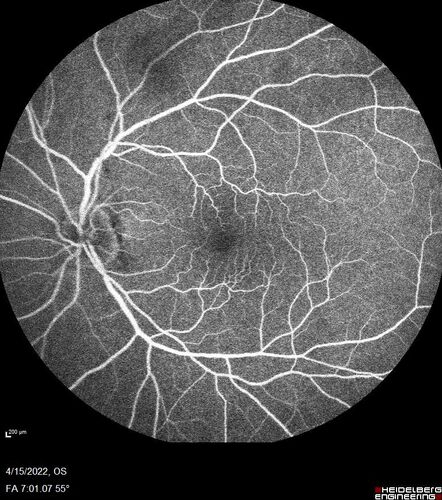

Toxoplasmosis right eye with diffuse retinal vascular whitening PCR confirmed

66 year old man The patient was doing fine until about 2-3 months ago.  He woke up with shadows and spots in the right eye.  Every blue moon he gets some pain in the right eye.  He has been getting treated with eye drops in the right eye.  Since this happened the vision is mostly the same.  Sometimes he sees better than other times.  He has not been treated with oral medications.

Medical history: none – Medications: none, ROS negative

VA OD: sc20/63-1 OS: sc20/20

IOP: TP: OD:15 OS:20

Negative labs: ACE, Lysozyme, RPR, HLA B27, Quant TB Gold, ESR (slight elevation of CRP)

PCR anterior chamber: negative herpes virus (HSV, VZV, CMV)

Positive for toxoplasmosis